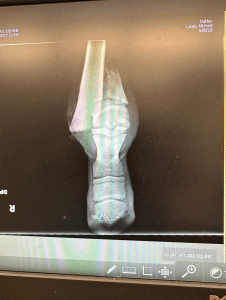

While traditional equine medical care might see injuries like hers as insurmountable, this filly’s tenacious spirit was a testament to an animal’s engrained will to survive. By the time she was discovered with her injury, she was facing:

- A severe and rapidly-spreading infection.

- A complex fracture of her cannon bone with severe soft tissue damage.

You and your family willingness to fight as long as Second Chance will to continued fighting. The xrays tell the store, the truth. Most would have ended it all. To spend the time making phone calls, asking questions, then traveling for days to safely transport her and her mom to Wyoming. Vet’s that were also willing to take on the challenge. Above and beyond, I am not sure you know any other way, to be honest. Second Chance looks unbelievable beautiful, strong and even after all that she has been through you can still see the fight in her sweet soft eyes. When you are around her…. she know you are her Hero and she shows you her love in her behavior around you.